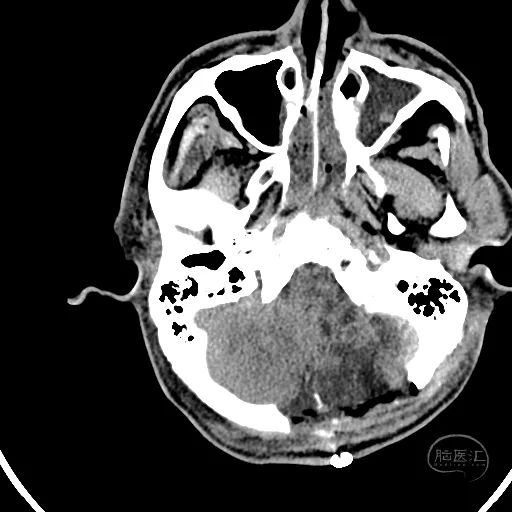

术后18天复查颅脑CT,显示小脑半球恢复良好,第四脑室清晰。

硬膜外血肿基本吸收。

额叶水肿减轻。

脑室稍扩张,骨窗张力较低。

患者GCS评分8分,已转入普通病房,继续康复治疗。